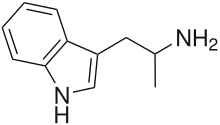

αMT | 1-(1H-Indol-3-yl)propan-2-amine | 299-26-3 |

α-Alkyltryptamines are a group of substituted tryptamines which possess an alkyl group, such as a methyl or ethyl group, attached at the alpha carbon, and in most cases no substitution on the amine nitrogen.[17][18][19] α-Alkylation of tryptamine makes it much more metabolically stable and resistant to degradation by monoamine oxidase, resulting in increased potency and greatly lengthened half-life.[19] This is analogous to α-methylation of phenethylamine into amphetamine.[19]

Many α-alkyltryptamines are drugs, acting as monoamine releasing agents, non-selective serotonin receptor agonists, and/or monoamine oxidase inhibitors,[20][21][22][23] and produce psychostimulant, entactogen, and/or psychedelic effects.[17][18][19] The most well-known of these agents are α-methyltryptamine (αMT) and α-ethyltryptamine (αET), both of which were used clinically as antidepressants for a brief period of time in the past and are abused as recreational drugs.[18][19] In accordance with its action as a dual releasing agent of serotonin and dopamine, αET has been found to produce serotonergic neurotoxicity similarly to amphetamines like MDMA and PCA, and the same is also likely to hold true for other serotonin and dopamine-releasing α-alkyltryptamines such as αMT, 5-MeO-αMT, and various others.[24]